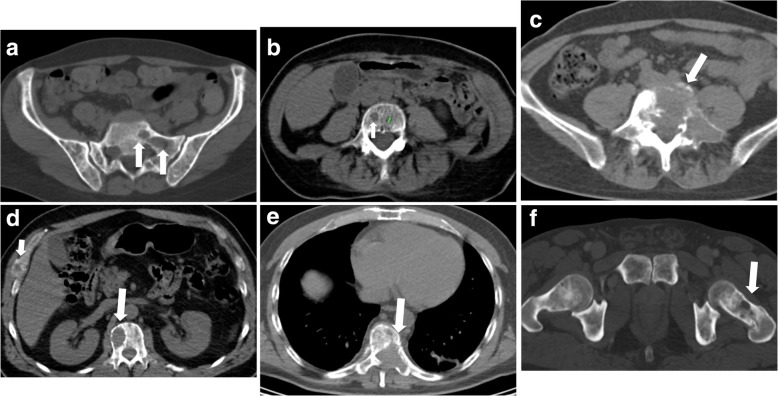

Spectrum of bone findings is reported in Fig. 1a.

Fig. 1.

Scoring bone damage and instability - spectrum of findings. a) Focal lytic lesions > 5 mm in diameter located at the left sacrum (white arrows). In this case the MSBDS was 2 (1 + 1). b) Single focal lytic lesion > 5 mm in the vertebral body (white arrow) with no vertebral collapse. The smaller focal lytic lesion (green line) is < 5 mm (no points in the MSBDS). In this case the MSBDS was 1. c) Large lytic lesion at the junctional spine (L5-S1) with collapse/involvement > 50%, posterolateral (facet, pedicle) involvement and more than 2/3 of bone diameter. In this case the MSBDS was 11 (3 + 3 + 2 + 3): the lesion was considered “high-risk” and immediate surgical or radiation oncologist consultation was warranted. In this case, there was also a possible spinal canal involvement. d) Lytic lesion > 5 mm (white arrow) at the junctional spine (thoraci spine) with collapse/involvement < 50%, and a small (small white arrow) focal lesion at the right rib cage. In this case the MSBDS was 6 (3 + 2 + 1): the lesion was considered “Medium risk:” 5–10 with medium risk of pathologic fracture. e) Large lytic lesion at the junctional spine (thoracic spine) with collapse/involvement > 50%, posterolateral (facet, pedicle) involvement and more than 2/3 of bone diameter. In this case the MSBDS was 11 (3 + 3 + 2 + 3): the lesion was considered “high-risk” and immediate surgical or radiation oncologist consultation was warranted. In this case, there is spinal canal involvement. f) Lytic lesion at the left femoral neck (white arrow). This lesion alone warrants 5 points in the MSBDS putting the patients in “medium risk” group